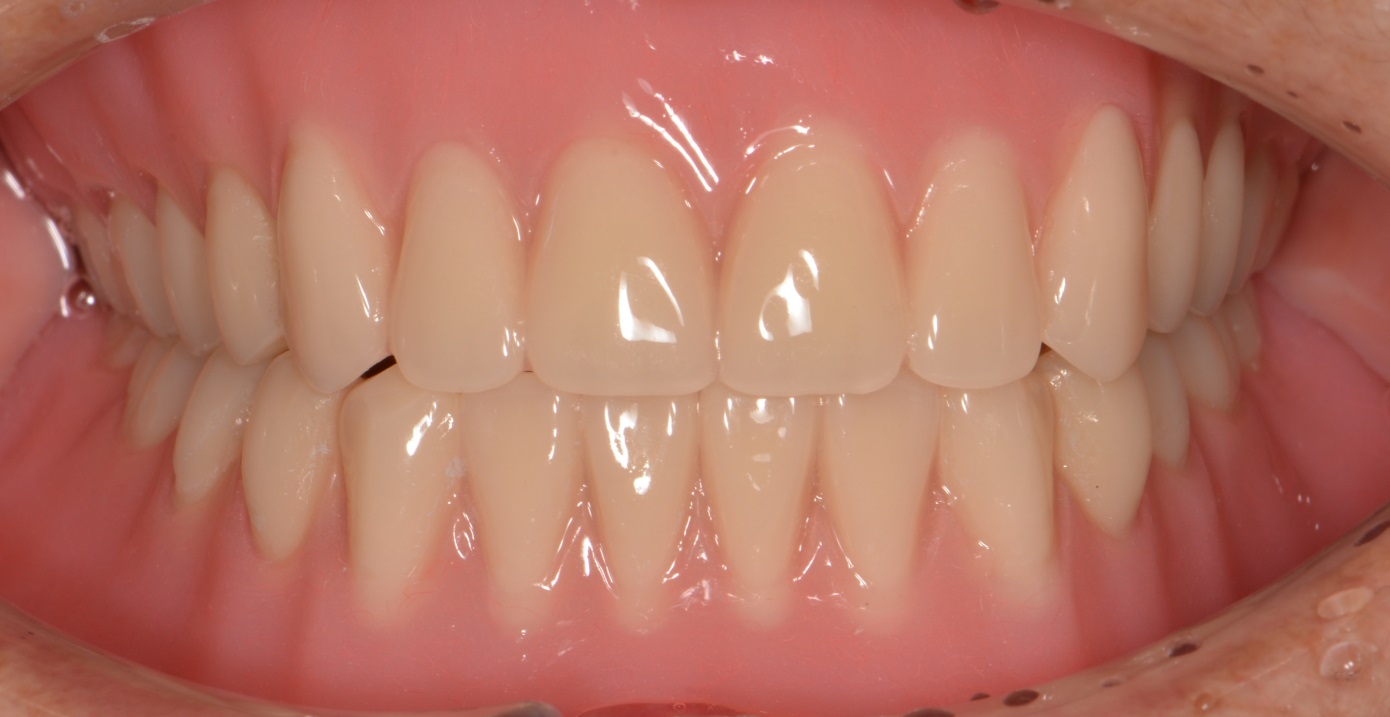

상,하악 완전틀니

After

안 좋은 치아를 모두 발치하고,

상,하악 모두 완전 틀니로 진행하였습니다.

완전틀니는 걱정하시는 것보다 심미적이고 이쁩니다. ^^